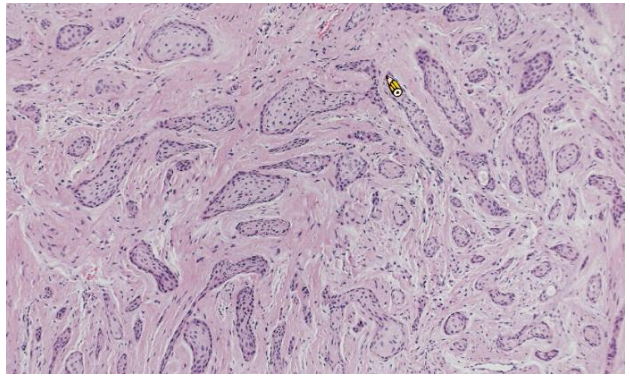

Odontogenic myxoma

齒源性黏液瘤

- 顎骨(下顎稍高) 25-30y

• 無痛腫脹,生長慢

• 難切乾淨,復發率高(25%)

• 推開牙根,牙根吸收

• 單或多房,多房分成 soap bubble, stepladder

• IHC: Actin 不太表現

alt text alt text

間質淡粉紅色,看不太到 collagen fiber